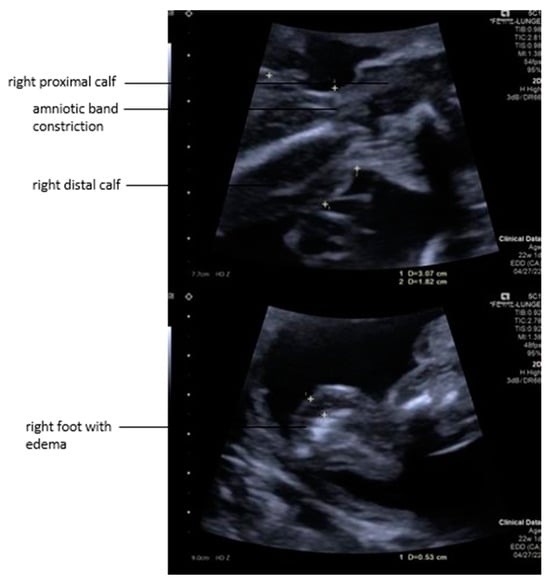

As the fetoscope was advanced into the amniotic cavity, fetoscopic inspection of the cavity and fetus was not possible as the amniotic fluid was severely blood-tainted and compromised visualization. Therefore, percutaneous partial amniotic carbon dioxide insufflation (PACI) was performed [13]. The mother was ventilated with target carbon dioxide levels within the physiologic range of 30–35 mmHg to prevent maternal and fetal respiratory acidosis during PACI. The insufflation pressure of the insufflator was increased in 2 mmHg increments until the release of carbon dioxide into the amniotic cavity was measurable. At this “opening pressure”, we removed the intrauterine fluid and exchanged its full volume with carbon dioxide. In this case, PACI was performed with an insufflation pressure of 8 mmHg; the flow rate was adjusted to 5 L/min. PACI permitted us to examine the whole amniotic cavity and the fetus (Figure 3 and Figure 4).

As already suspected in the ultrasound examination, the fetus was seen to lie in a blood-tainted amniotic cavity covered by amniotic material (Figure 3). As the left foot was protruding through a hole in the abrupted placenta, the fetus might have torn it off with a wrong movement, which, in the worst case, could have resulted in severe maternal hemorrhage. The umbilical cord was surrounded by multiple strings of the detached amniotic sac, and the proximal right calf was constricted by a tight, circumferential amniotic band (Figure 4).

Figure 3. After entry to the amniotic cavity via three 11-Fr trocars, partial carbon dioxide insufflation (PACI) allowed for visualization of the fetal head, lying in a blood-tainted amniotic cavity and covered by the largely separated amniotic membrane.